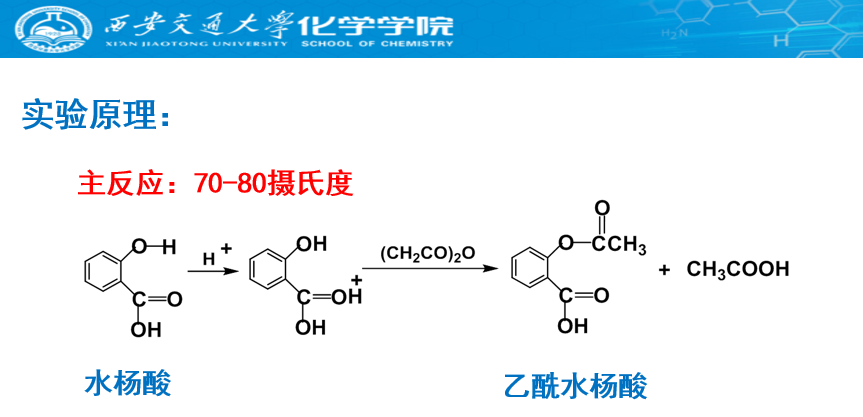

阿司匹林是以乙酸酐为酰化试剂,在酸的催化下,得到了水杨酸的乙酰化产物。近年来,人们发现阿司匹林除了具有解热、镇痛、消炎的作用外,小剂量的阿司匹林还可以抑制血小板聚集,长期服用能够有效减少心脑血管疾病的发生,治疗神经性疾病,解决抗癌药物顺铂耐药性问题等。研究表明,长期服用阿司匹林的患者,罹患严重心血管疾病的风险降低了12%,但发生大出血的概率提高了29%。“祸兮,福之所倚;福兮,祸之所伏”。